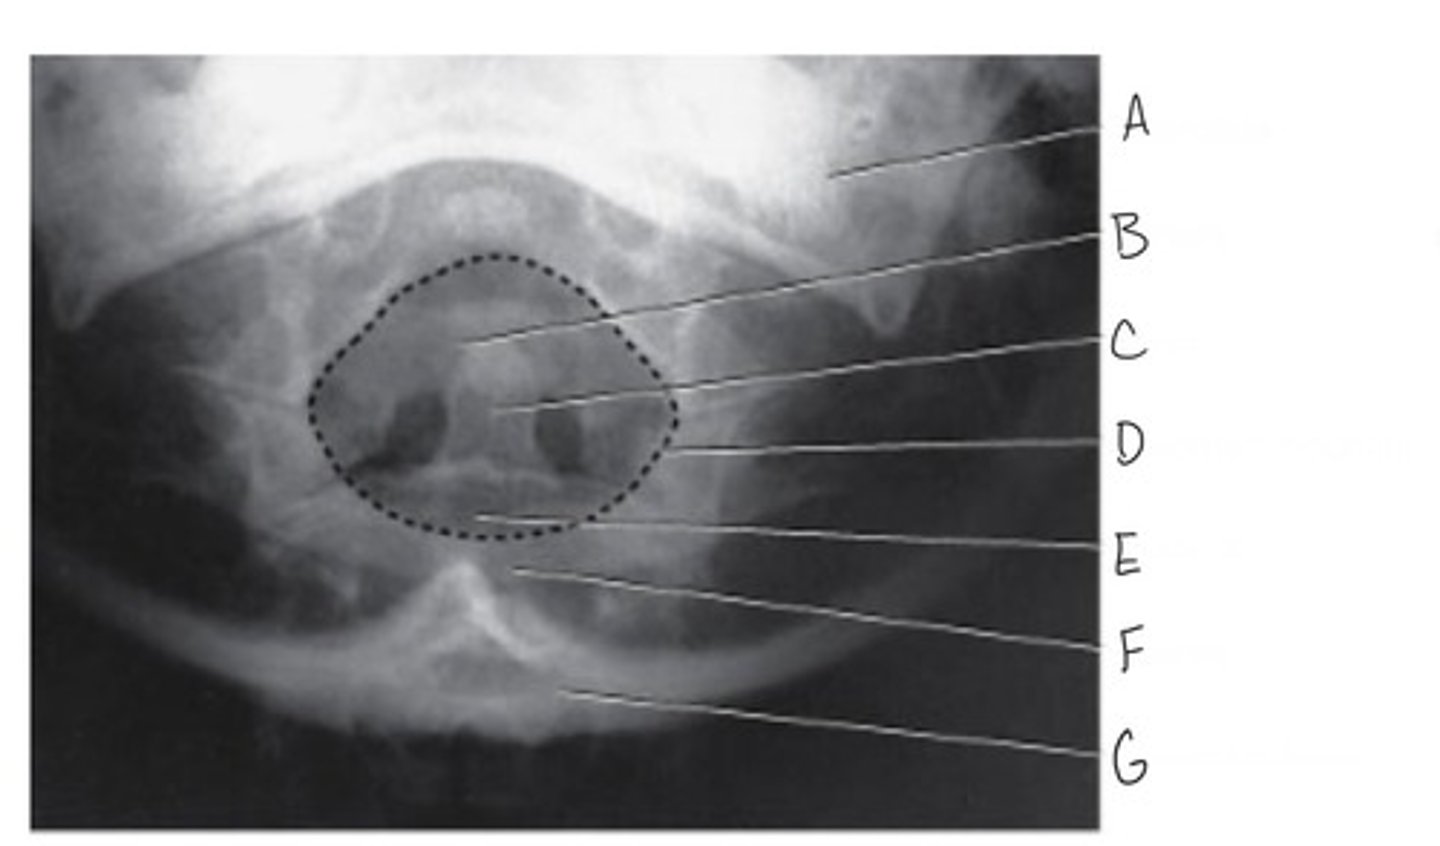

AP (Fuchs method) projection of the cervical spine: Atlas & Axis

What is this radiograph projection?

Mandible

What is A?

Anterior arch of atlas

What is B?

Dens (odontoid process)

What is C?

Foramen magnum

What is D?

Body of axis

What is E?

Posterior arch of C1

What is F?

Occipital bone

What is G?